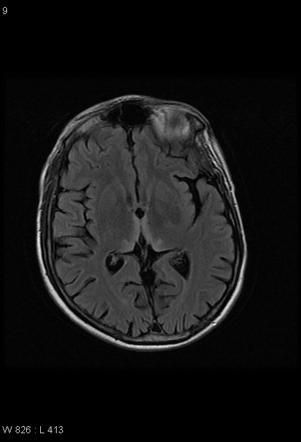

Uncal shift

vs

Uncal herniation

A

• uncal shift - just shifted out

• uncal herniation - bad - on coronal images, the uncus is on the other side of the tentorium! - blown pupil due to compression on the cisternal portion of the CNIII

• death occurs when there is mass effect on the adjacent midbrain